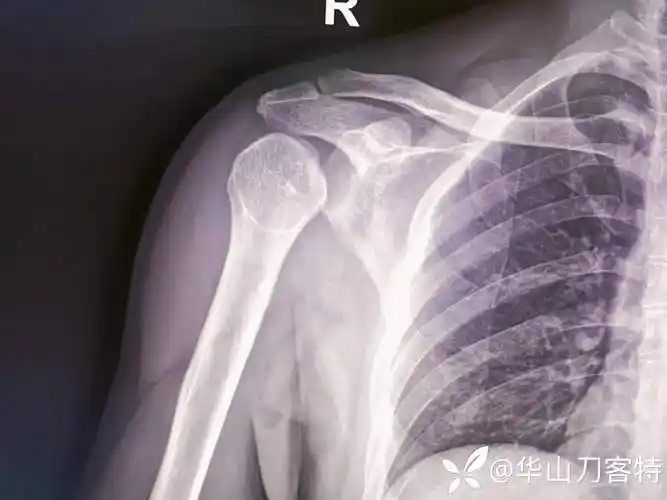

灯泡征高度提示肩关节后脱位